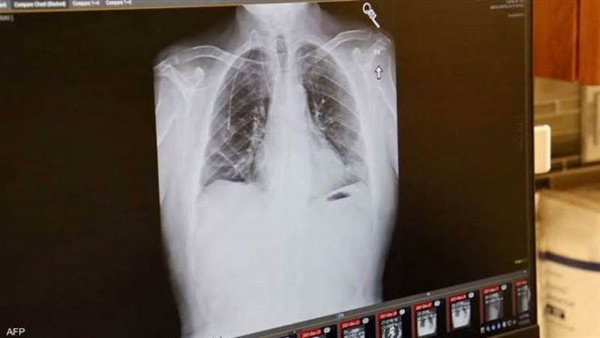

علماء يكشفون سر انتشار سرطان الرئة لدى غير المدخنين

سرطان الرئة يصيب غير المدخنين ارتبطت الإصابة بسرطان الرئة منذ عقود بالتدخين، لكن زيادة نسبة الإصابة بهذا المرض لدى غير المدخنين دفع عدد من العلماء لتصنيفه كمرض مستقل يختلف عن فئات السرطان المعروفة سابقا، وله خصائص تميزه.